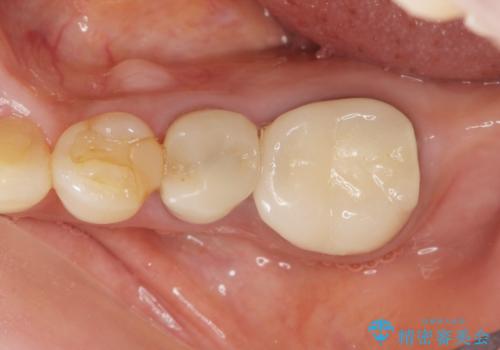

親知らずの移植 4年半経過症例 70代女性

- 親知らずの移植治療から4年半経過した患者様です。

移植した親知らずは全く問題ないそうで、「まるで自分の歯のようです。本当にすごい技術ですね。」とおっしゃって下さいました。

歯肉の腫脹や退縮、動揺も認められませんでした。

4年半前に行った自家歯牙移植に大変ご満足頂き、ご家族も紹介して下さいました。

自家歯牙移植は40歳以上の場合、若年者に比べ成功率が低くなるとの報告もありますが、状態によっては移植が可能な場合もあります。